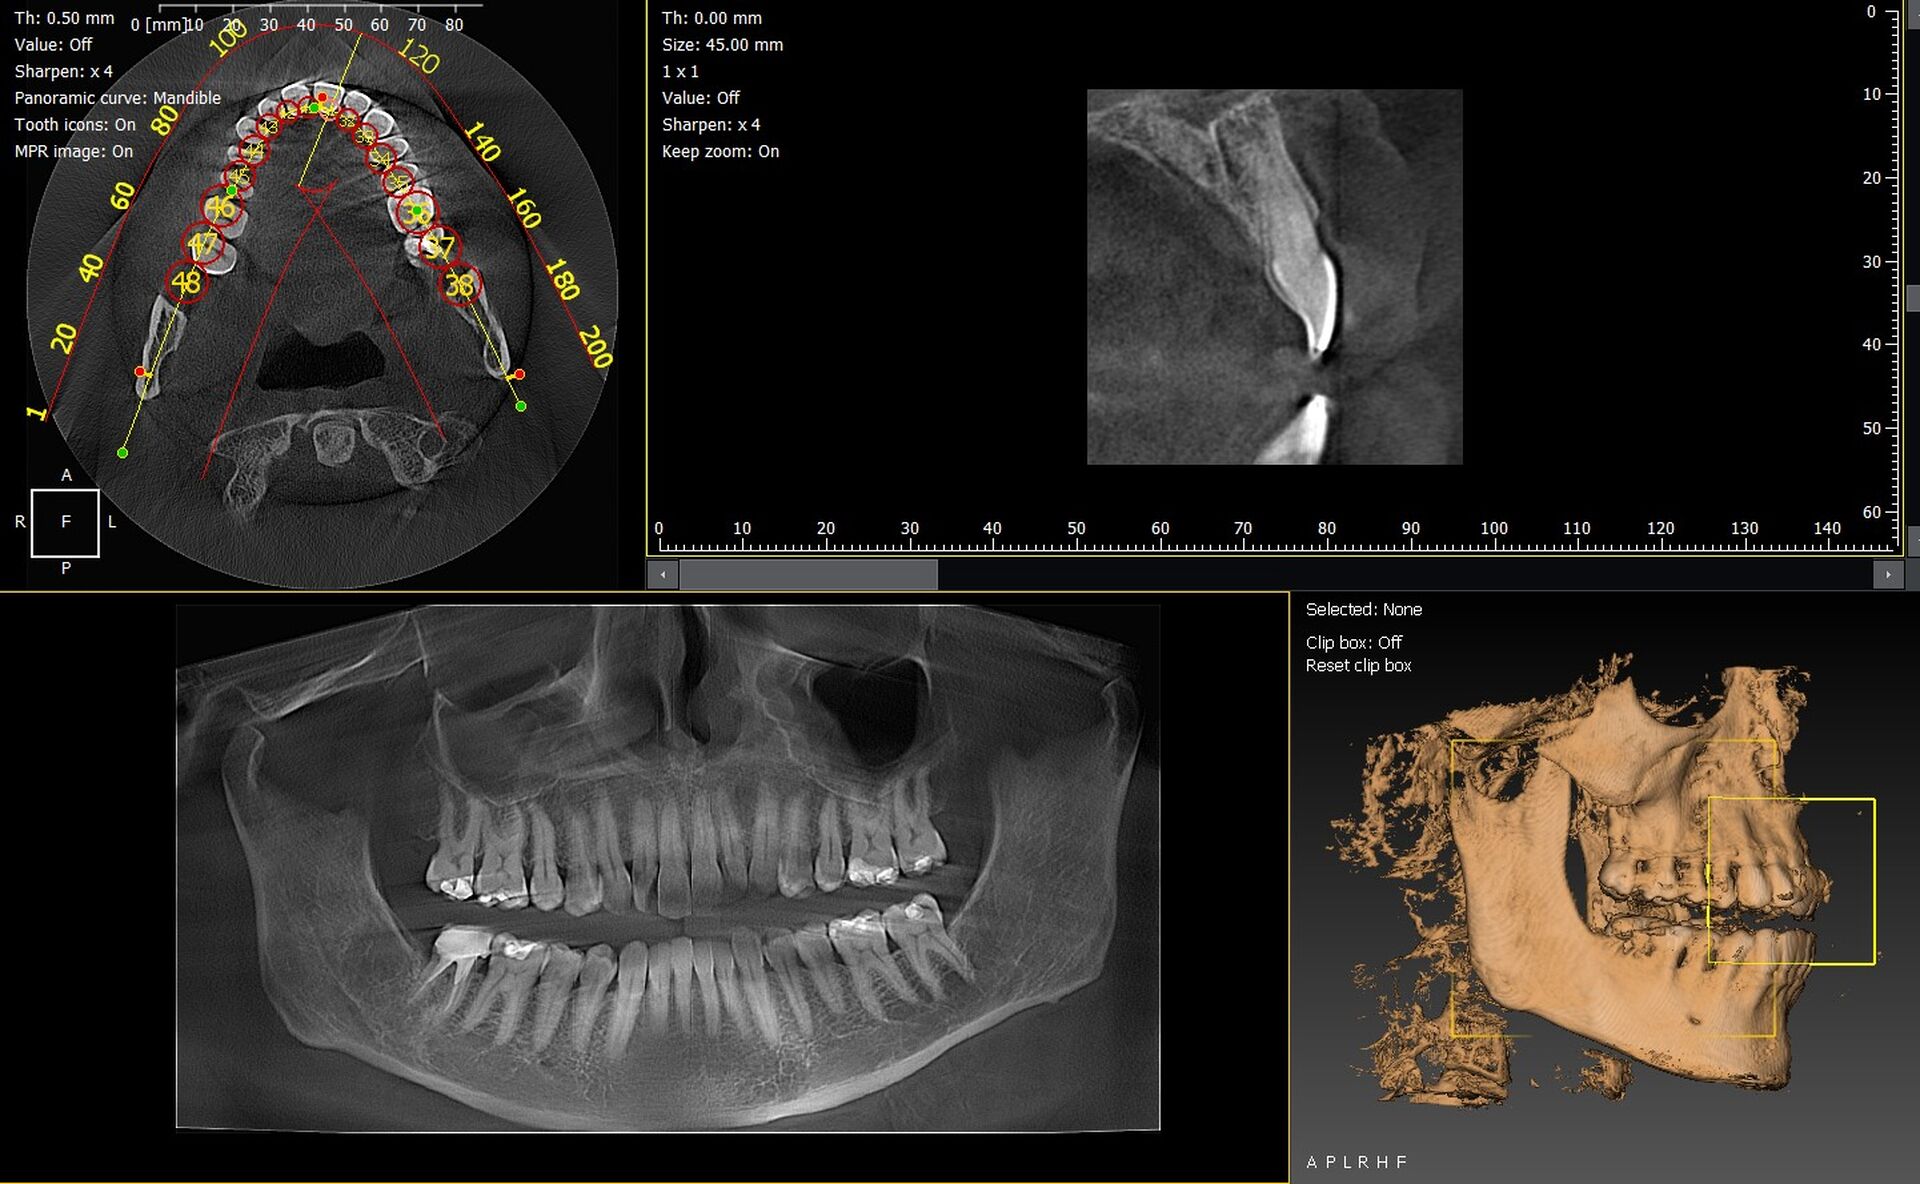

Les cabinets dentaires d’Aubagne et du département des Bouches-du-Rhône (13) modernisent leur plateau technique grâce à des solutions d’imagerie 3D fiables, performantes et adaptées aux besoins cliniques actuels. Les panoramiques CBCT 3D VistaVox de Dürr Dental et l’Owandy I-Max 3D figurent parmi les appareils les plus avancés, offrant une précision diagnostique remarquable et une qualité d’image de très haut niveau.

VistaVox 3D : précision et champ d’examen optimisé

Le VistaVox 3D se distingue par :

• un volume d’examen adapté à l’anatomie dentaire,

• une haute résolution idéale pour implantologie et endodontie,

• une dose maîtrisée,

• un positionnement patient rapide et ergonomique.

Une solution parfaitement adaptée aux cabinets recherchant une imagerie haut de gamme dans le 13.